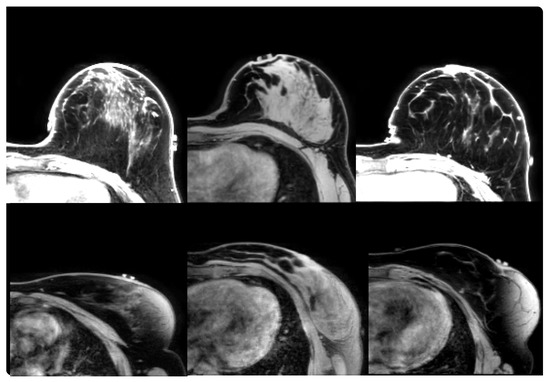

2.1.2. Prone-Supine